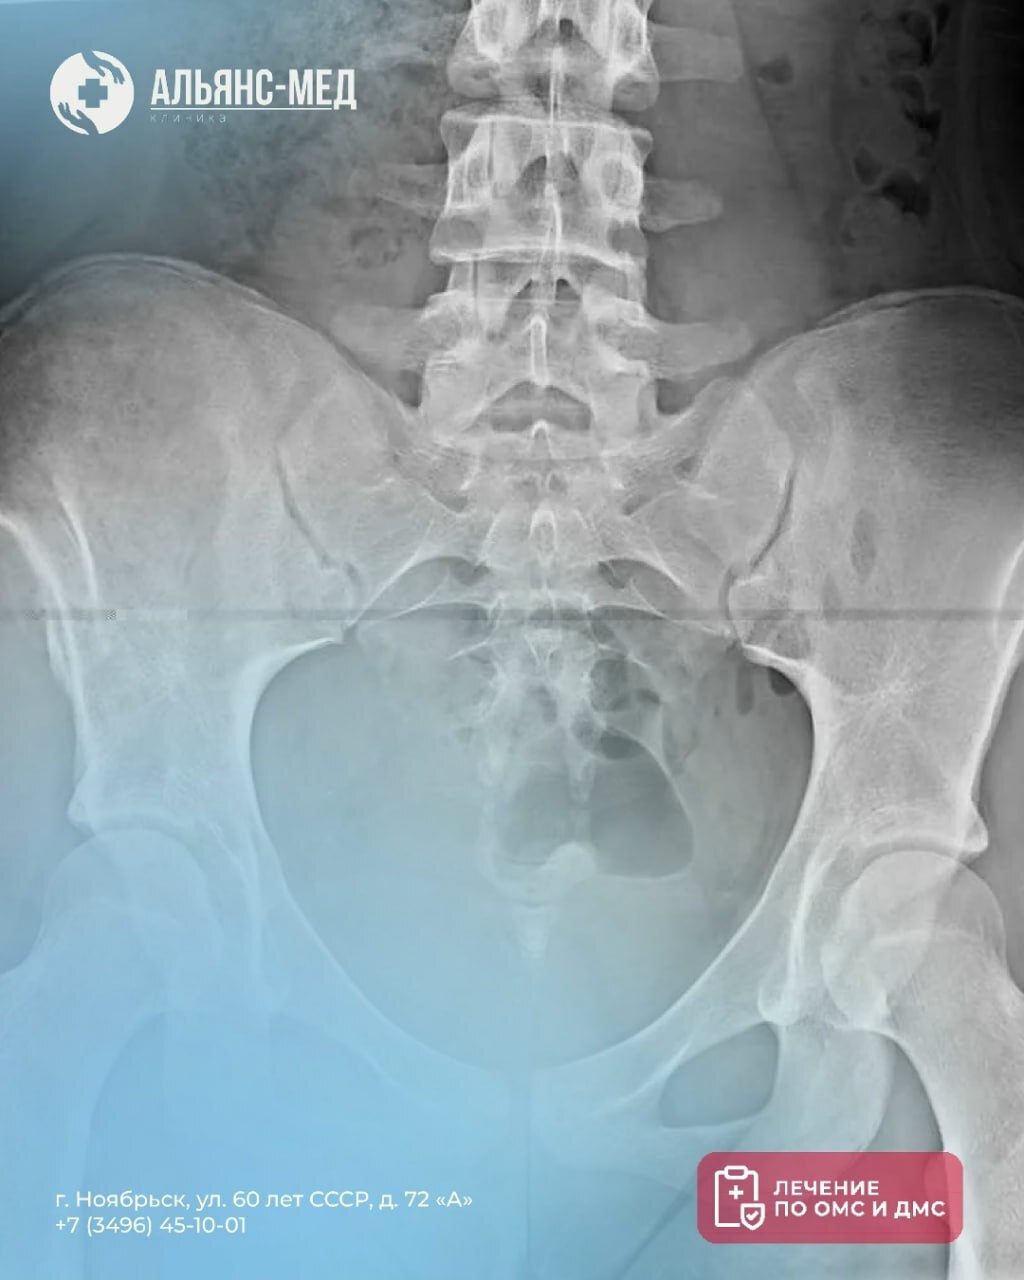

Не ждите, пока боль ограничит вашу жизнь. Рентген крестца и копчика — это надежный способ выявить проблему и начать правильное лечение.

Что покажет диагностика:

➡️ Трещины, переломы, смещения

➡️ Остеохондроз и другие заболевания

➡️ Врожденные аномалии